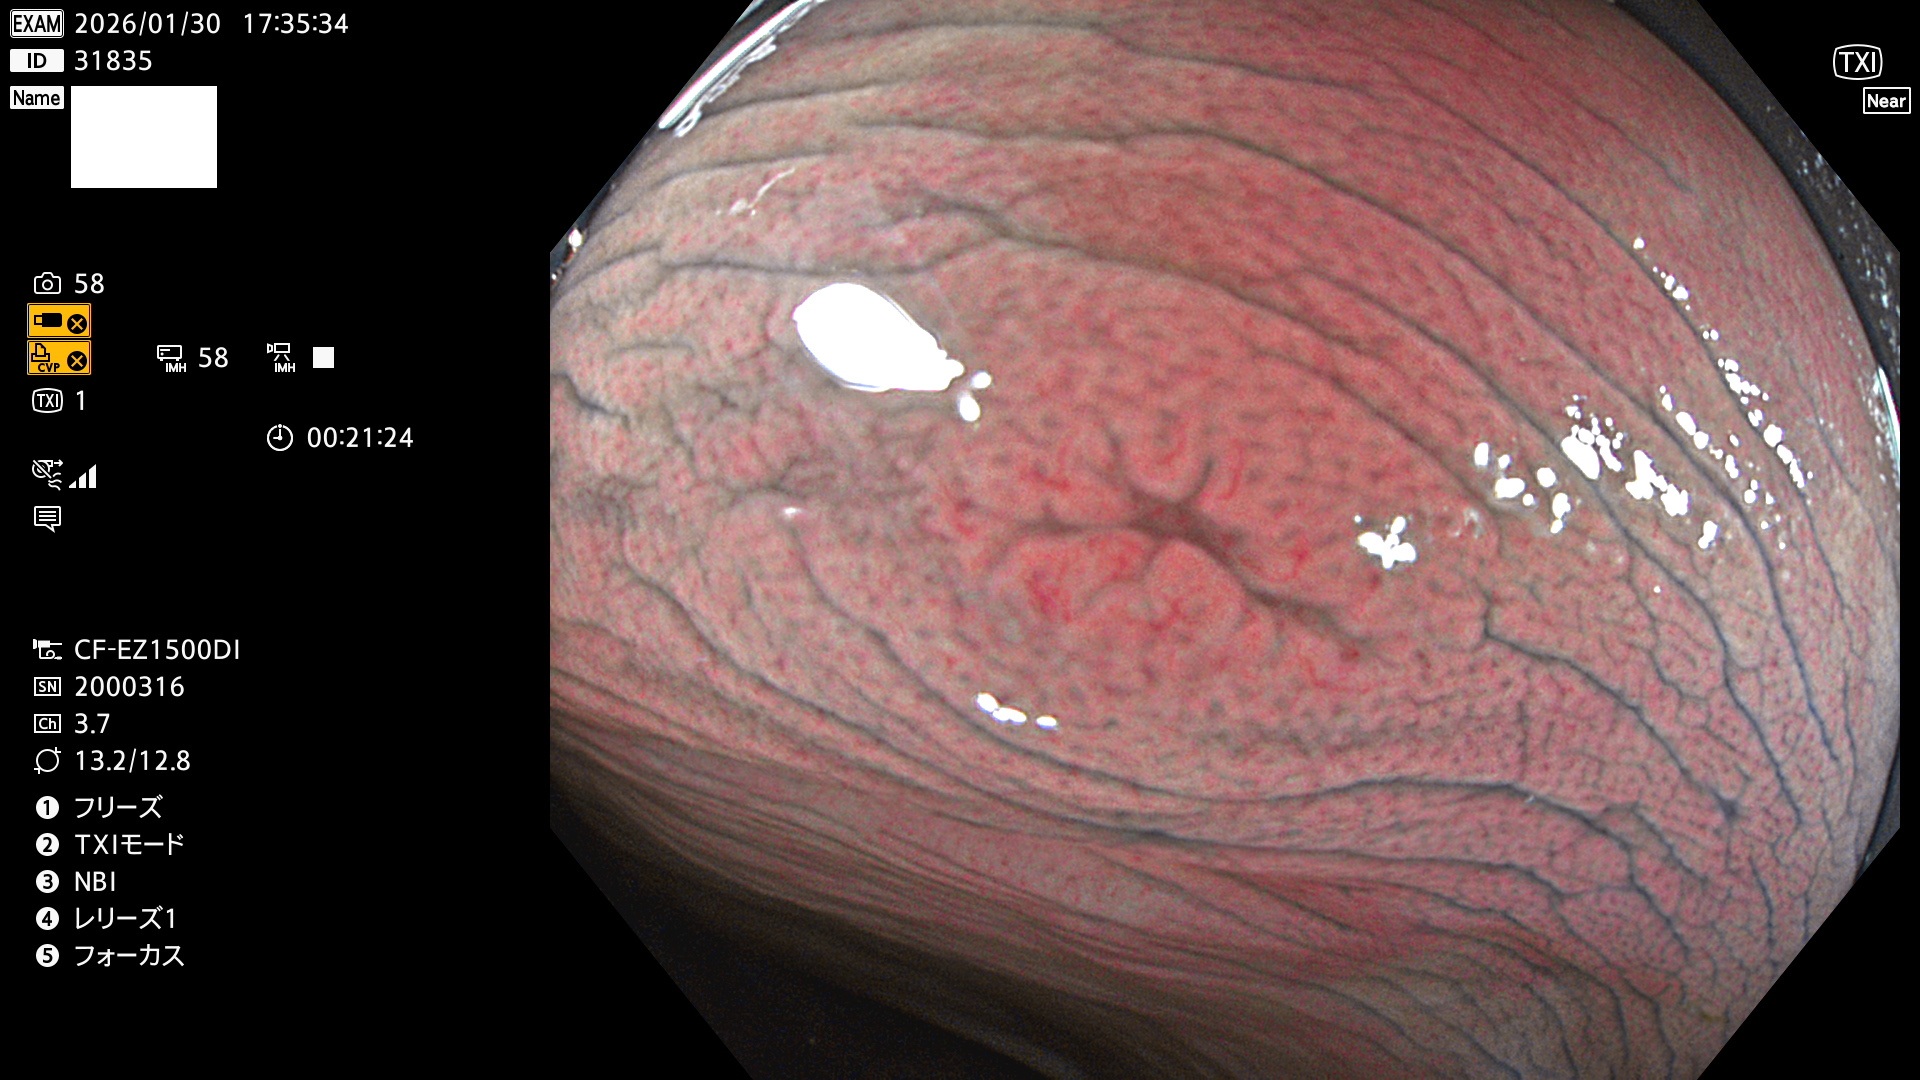

完全に平坦な物をUb、陥凹している物をUcと呼びます。Ubは認識が困難で、Ucはびらん(炎症)と紛らわしいために見落とされやすく、「内視鏡後・大腸癌」の原因になります。

毎週の検査(木・金・土・日)に発見されたUbとUc型・腺腫を、その週の日曜の夜にUPし1週間、提示します。

2026年1月29日〜2月1日の4日間(40件)10個 (Uc_ADR=10個/40人=25%)